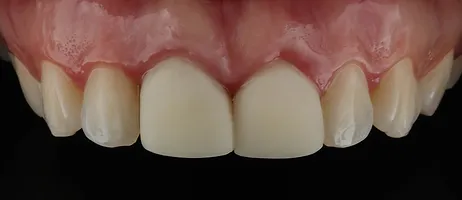

Estava diante de um grande desafio: devolver a arquitetura gengival alterada pelas facetas inadequadas já presentes tendo que realizar um implante dentário na região de incisivo central de uma paciente jovem, com sorriso gengival, filha de dentista e que só queria mudar esses dois dentes.

Realizamos então a exodontia do incisivo central superior direito, seguido de implante, enxerto 100% com biomaterial, provisório imediato e posterior troca da faceta do incisivo central superior esquerdo. A maior preocupação era utilizar uma técnica cirúrgica que mantivesse o alinhamento da gengiva com os dentes vizinhos e uma reabilitação protética que escondesse o implante e a faceta do dente vizinho no conjunto do sorriso.